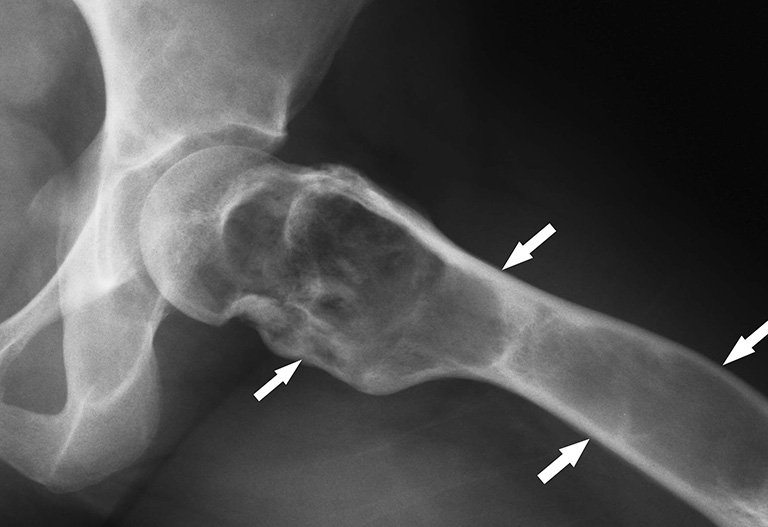

Bệnh có thể phát sinh ở bất kỳ phần xương nào trong cơ thể. Tuy nhiên, các vị trí như xương chậu, đầu gối, phần đầu của các xương dài (như xương cánh tay, xương đùi, xương chày và xương bắp chân), xương ức và vùng xương gần cột sống thường gặp nhất.

Trong 70% trường hợp u phình mạch xương, tổn thương ban đầu xuất phát từ sự tăng sinh mạch máu trong u. Còn lại 30% trường hợp phát triển từ các loại u khác như u tế bào khổng lồ, u sụn, u xương,…

X quang thường là phương pháp chẩn đoán đầu tiên được sử dụng khi có triệu chứng mới xuất hiện. U nang xương phình mạch có một số đặc điểm đặc trưng trên hình ảnh X quang:

Hình ảnh X quang thường không đủ để mô tả u nang xương phình mạch, nên cần phối hợp với chụp cộng hưởng từ để đưa ra chẩn đoán chính xác. MRI giúp xác định tính chất của u nang bằng cách:

Các hình ảnh trên phim X quang hoặc phim MRI không đặc trưng đối với nang xương phình mạch, vì chúng cũng có thể xuất hiện ở các loại u xương khác như u tế bào khổng lồ, nang xương đơn độc hoặc ung thư xương dạng xương.

Đặc biệt, ung thư xương dạng xương có thể gây ra sự phình tĩnh mạch, làm cho việc phân biệt với nang xương phình mạch trên hình ảnh trở nên khó khăn. Vì vậy, việc tiến hành sinh thiết mô u để phân tích là biện pháp chẩn đoán chính xác nhất.